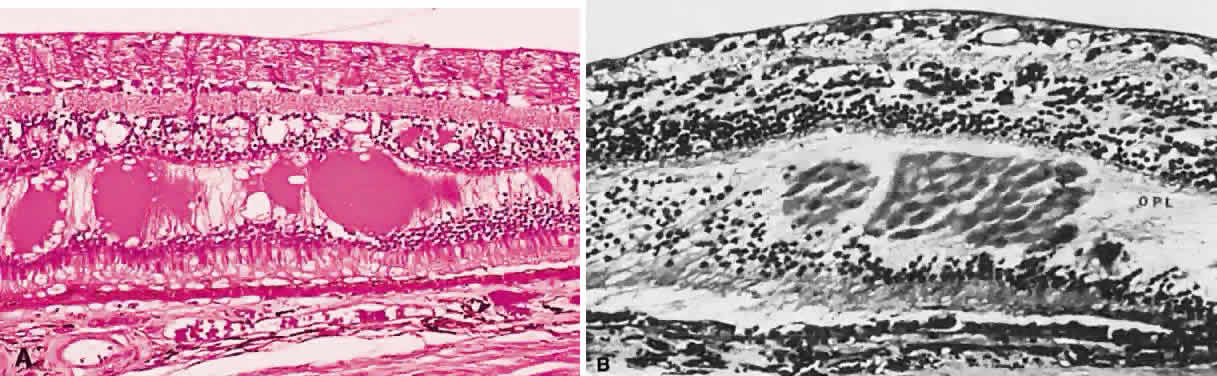

Fig. 17. A. A histologic section stained with H & E demonstrating vascularized

membranes on the disc and retina. Tractional retinal detachment is present. Notice

the subretinal fluid (amorphous eosinophilic material). B. Fundus photograph of fibrous tissue emanating from the disc in patient

with proliferative diabetic retinopathy. The disc is pale; the macula

is edematous with exudate. Pigmented laser spots are visible temporally. Fig. 17. A. A histologic section stained with H & E demonstrating vascularized

membranes on the disc and retina. Tractional retinal detachment is present. Notice

the subretinal fluid (amorphous eosinophilic material). B. Fundus photograph of fibrous tissue emanating from the disc in patient

with proliferative diabetic retinopathy. The disc is pale; the macula

is edematous with exudate. Pigmented laser spots are visible temporally.